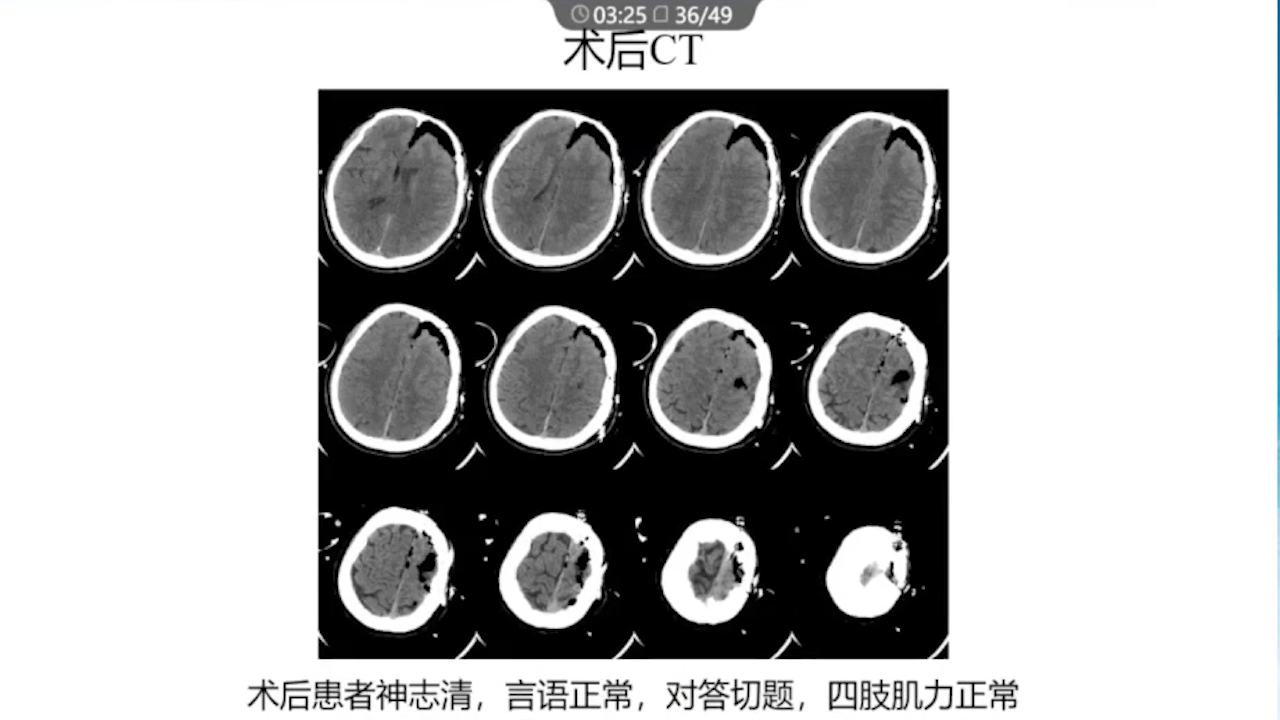

8、术后积极进行脱水治疗:如果术后脱水不及时,将可能发生严重的脑水肿,导致功能区脑组织受压、静脉回流障碍等一系列的严重反应。